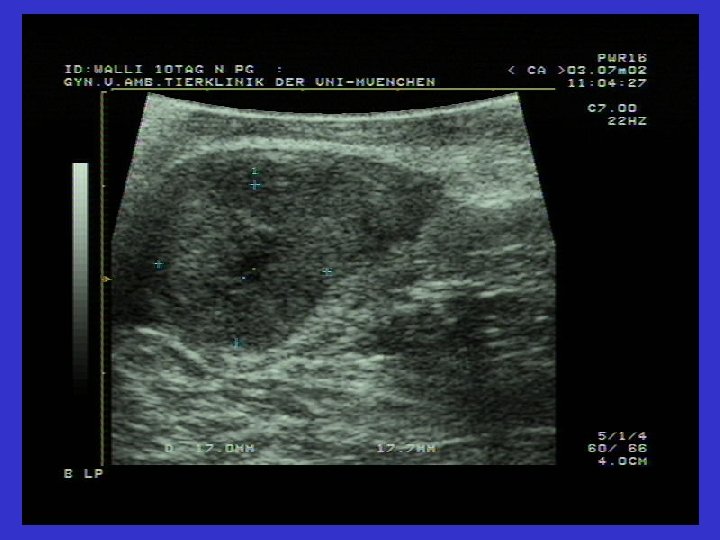

Graaf follikülü ve Follikül Theka kistlerinin karşılaştırmalı ultrasonografik görüntüsü

Follikül lutein kistlerinin tanısı • • Follikül 2, 5 cm den büyüktür Anöstrus gözlenir Persistenz (=kalıcıdır); genellikle soliterdir Ultrasonografi: ortada anekojen; çevresi hipoekojen (gri) (>3 mm) • P 4= serum (1 ng/ml=3, 18 nmol/L) süt= 10 ng/ml den yüksek (Aslan, 2000) • Uterus yangısı ile birlikte görülebilirler (Arbeiter ve ark. , 1991; Zerbe ve ark. , 1999)

Ovaryum luteal kistlerinin ultrasonografik görüntüsü Solda ovaryum luteal kisti (31 mm). Gri Hipoekojenik alan çepeçevre seçiliyor.